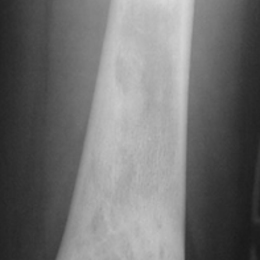

Aneurysmal Bone Cysts are benign aggressive tumors that destroy bone. They most commonly affect the spine and growth plates of the femur and tibia.